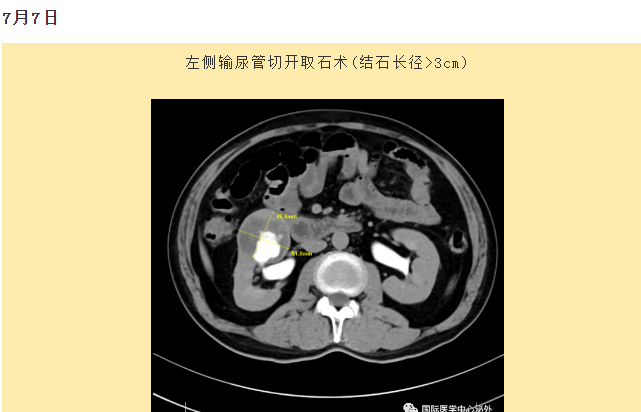

西安國際醫(yī)學中心醫(yī)院順利完成了達芬奇Xi(第四代)機器人裝機。7月6日—7月15日,泌尿外科成功完成了達芬奇Xi(第四代)機器人手術6例,標志著科室微創(chuàng)外科邁入新時代,造福萬千患者。